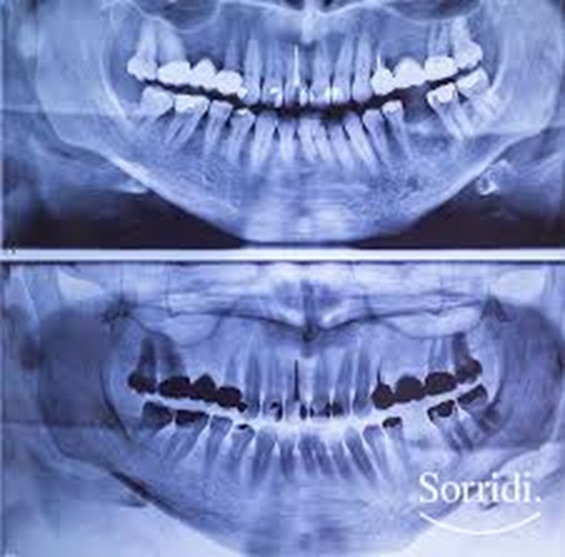

Il camice di piombo è una protezione fondamentale durante la radiografia l’ortopanoramica perché riduce l’esposizione del corpo a radiazioni ionizzanti, proteggendo tessuti e organi sensibili non interessati dall’indagine. Anche se la dose erogata per un ortopanoramica è bassa rispetto ad altre procedure radiologiche, la protezione rimane necessaria per seguire il principio ALARA (As Low As Reasonably Achievable): mantenere la dose il più bassa possibile.

Il camice di piombo è progettato per coprire le aree non in esame; durante l’ortopanoramica il sensore è focalizzato sulla bocca e la mandibola, quindi proteggere il collo e il tronco riduce un’esposizione laterale o diffusa. Inoltre, l’impiego del camice è parte delle normative e delle linee guida radiologiche che richiedono l’adozione di misure di protezione collettiva e individuale nei servizi sanitari.